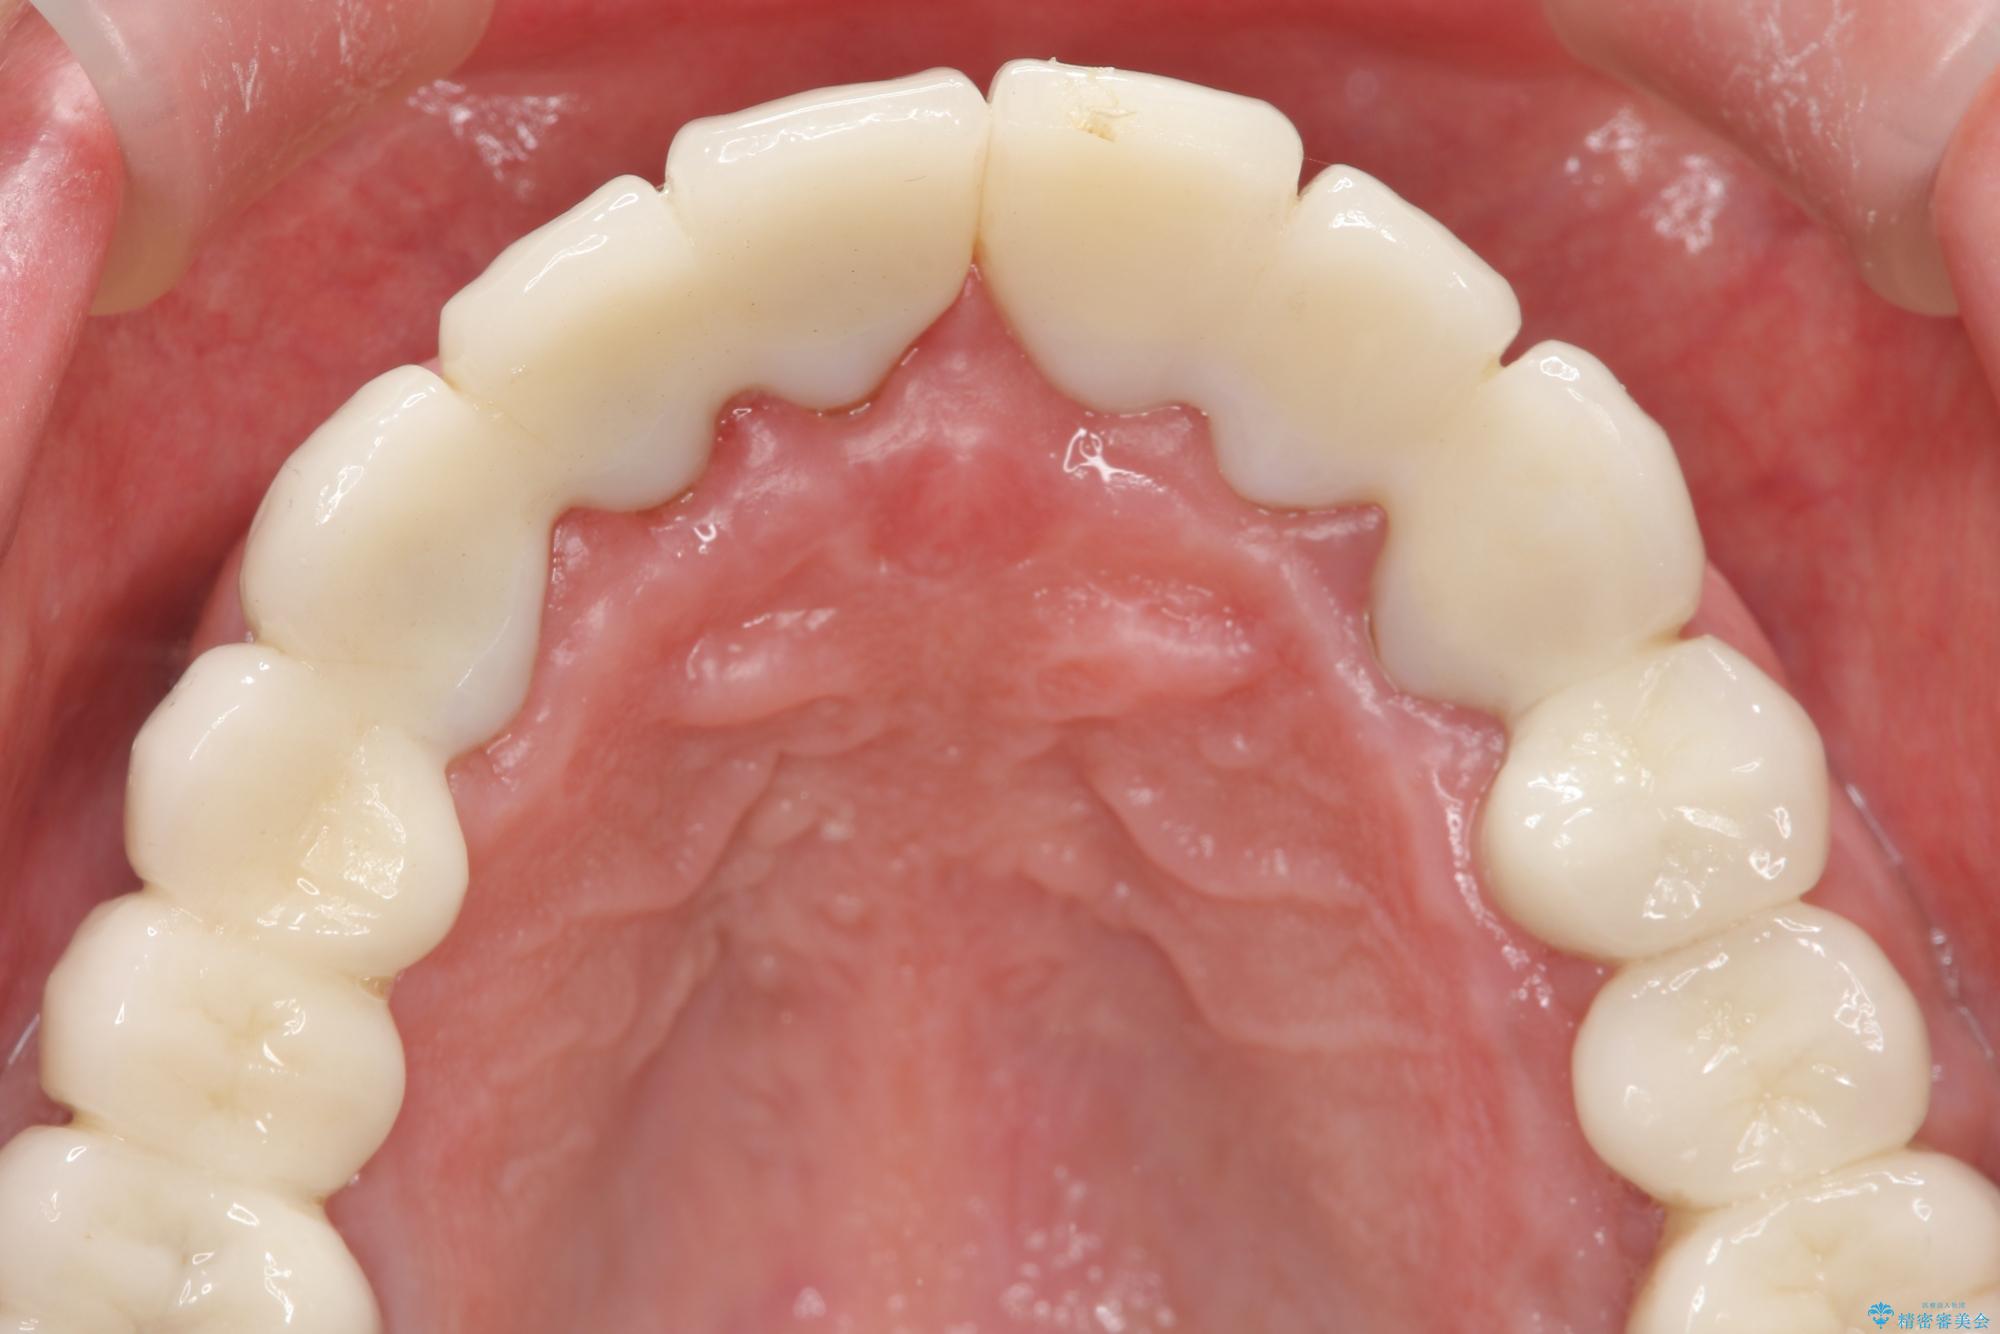

セラミッククラウンを除去し仮歯を装着し、歯周外科手術を行い歯ぐきの状態を改善したのち、適合の良いセラミッククラウンを再作製をする治療計画としました。

- 90.2万円(ジルコニアクラウン×6・仮歯×6 ・歯周外科手術)費用は治療当時の料金となります